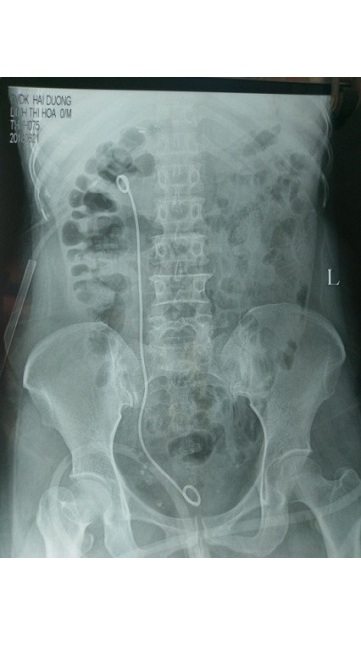

Trước tán sỏi

Sỏi được tán

Sau tán sỏi